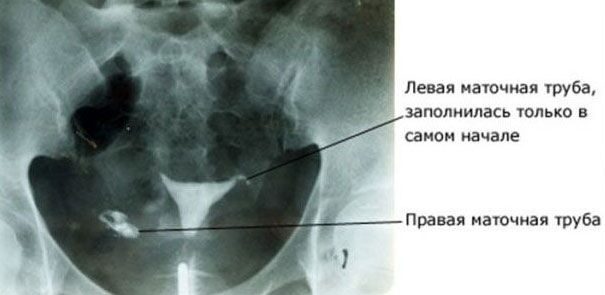

В большинстве случаев маточные трубы не визуализируются при УЗИ. При УЗИ видны расширенные маточные трубы. В норме — их не видно. А спайки внутри маточных труб можно выявить, проводя исследования на проходимость маточных труб, например, ГСГ (гистеросальпингография).